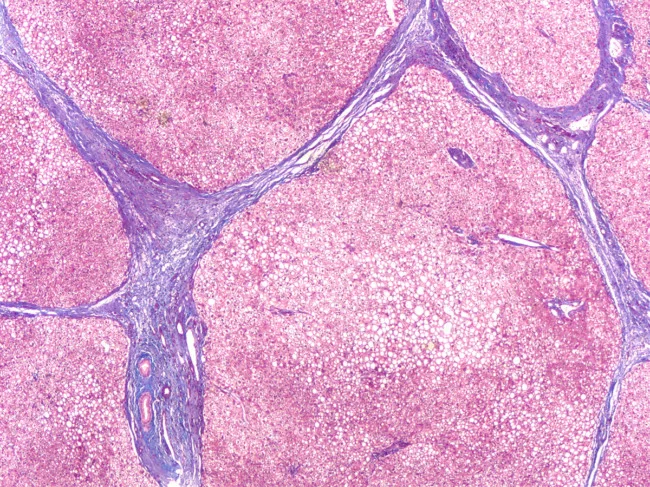

Photomicrograph of liver biopsy in a patient with cirrhosis, showing bridging septal fibrosis and regenerative nodules.

Australian scientists explore MERTK as a target against organ fibrosis

A small molecule could provide a new therapeutic approach against organ fibrosis. Using genome-wide association (GWA) assays, a group of researchers from the Westmead Institute for Medical Research in Sydney identified Mer tyrosine kinase (MERTK) as a candidate to study fibrosis and showed that its inhibition with the experimental compound reduced this condition in mouse models’ liver, kidneys and lungs. “There were some studies on the role of MERTK in liver fibrosis, but its therapeutic potential for various organ fibrosis has not been explored before. This study provides unequivocal evidence that MERTK is a potent nodal regulator of fibrosis supported by detailed mechanistic studies,” the senior author Mohammed Eslam told BioWorld. Read More